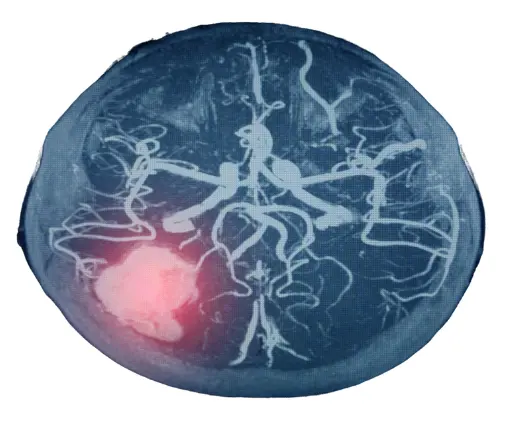

오늘은 뇌경색 초기증상, 원인 및 치료 방법에 대해 포스팅을 해보겠습니다. 뇌경색은 뇌에 혈액을 공급하는 혈관이 터지거나 막힘으로 인해 산소공급이 차단되어 뇌조직이 손상되는 증상을 말합니다.

뇌경색 원인 2. 뇌동맥류

뇌동맥류는 뇌혈관이 약해져 부풀어 오른 것을 말합니다. 뇌동맥류가 터지면 뇌출혈이 발생할 수 있습니다.

뇌경색 치료방법 2 . 혈관내 혈전 제거술

혈전용해제 치료가 불가능한 경우에는 혈관을 직접 뚫어주는 수술 치료를 시행하기도 합니다. 혈관내 혈전 제거술은 카테터를 혈관에 삽입하여 혈전을 제거하는 방법입니다. 혈관내 혈전 제거술은 혈전용해제 치료보다 효과가 좋지만, 수술의 위험성도 있습니다.